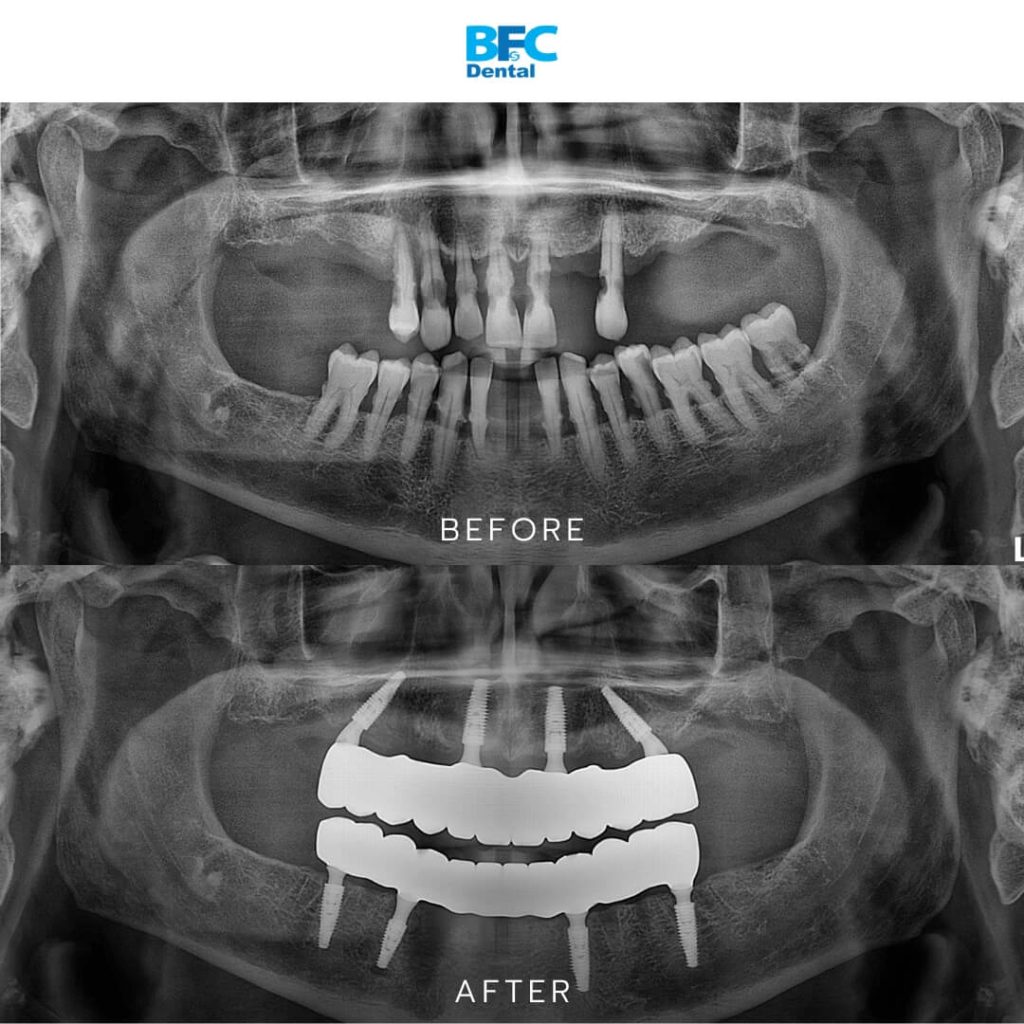

A recent case exemplifies the devastating effects of advanced periodontal disease and the remarkable transformation possible through modern dental implant protocols. This patient arrived with only a few remaining natural teeth, all infected and mobile beyond saving. Gum recession was visibly severe, and infection had destroyed substantial amounts of bone in both upper and lower jaws.

After comprehensive evaluation, the dental team determined that preserving the remaining teeth would compromise long-term oral health. The treatment plan involved extracting all remaining teeth and implementing full mouth All-on-4 dental implant restoration to completely rehabilitate the oral cavity. The outcome proved transformative: within just 24 hours, the patient could smile confidently again with a complete set of beautiful new teeth, healthy gums, and zero residual infection.

The All-on-4 technique involves placing just four dental implants per jaw to support a complete fixed bridge, offering a streamlined yet highly effective approach to full mouth restoration. The treatment unfolds through carefully coordinated phases designed to maximize efficiency while ensuring optimal outcomes.

• Placement of Dental Implants: Four implants were placed in the upper jaw and four in the lower jaw. Each implant was positioned with precision to ensure strong anchorage and optimal distribution of biting forces.